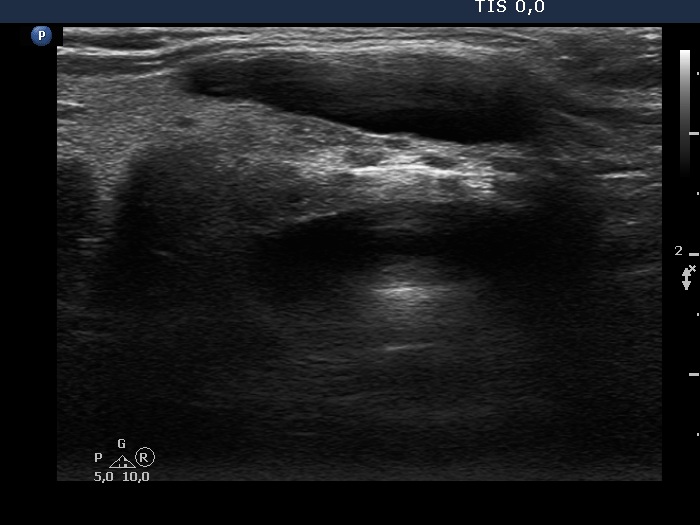

Intranodular hyperechogenic figures - case 1158 (ultrasonographic picture 6)

Isthmus, another longitudinal scan.